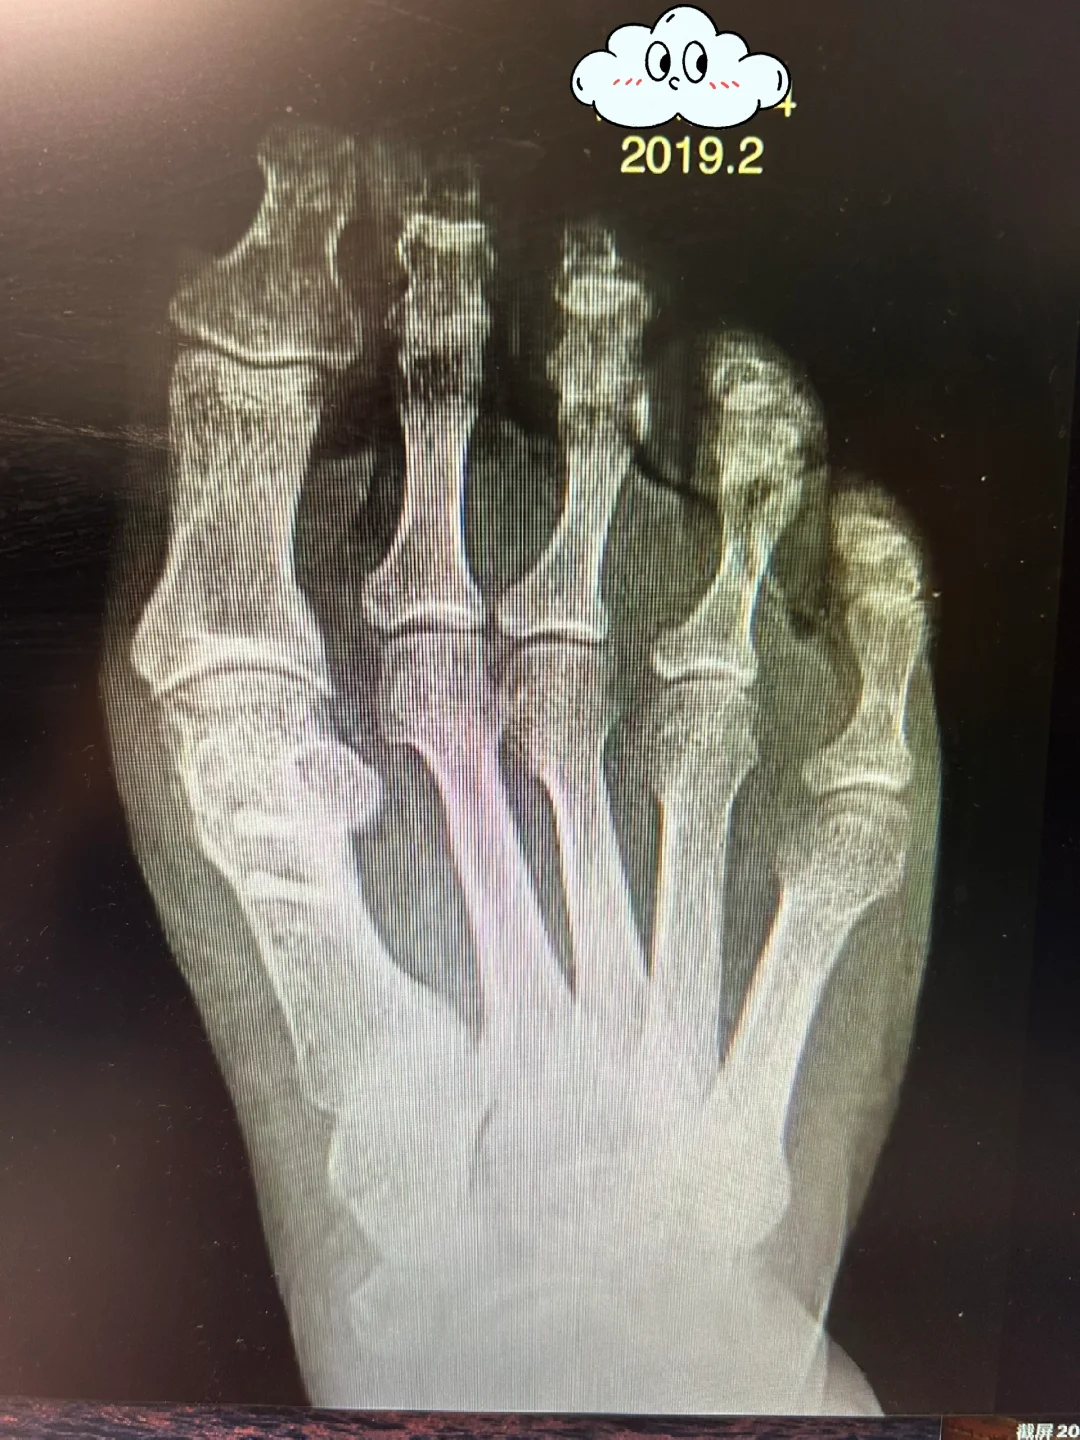

还有一种情况,手术后挺好的,很直,但是慢慢地歪了。这种情况又分两种,一种是复发,而另一种是术后角度的丢失。但是这两种情况并没有明确的界限。就像图中的照片,术后看片子很好啊!关节都很好,其实,这里有个很大的隐患,就是1.2趾之间的间隙,这个间隙不会一直存在,如果二趾靠过来,那就直了,如果拇趾倒过去,那就惨了。这种情况,绝大部分是拇趾倒过去,所以,这种片子一定要术后戴分趾器,五趾袜都不够,要分趾器维持,维持足够久,在关节周围形成瘢痕包绕,会减少术后的丢失。但是,也有很大比例最终结果仍然是丢失。所以,网络上你看那些夹着分趾器的外观照片是不准确的,多年以后没有间隙才是最终结果,因为很少有人能终身夹分趾器。

那么,图中的片子为什么丢失呢?Chevron平推术式,就这样的效果。比术前强,但不直。